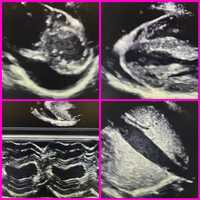

This is a moderate sized pericardial effusion that is located posteriorly to the heart. The inferior vena cava is dilated, greater (50%) inspiratory change is a commonly observed sign in significant effusion cases. The inflow respiratory variations of the mitral valve and tricuspid valve are also very important indicators for tamponade.

The pericardium has two layers, and the space between the layers normally contains a thin layer of fluid. But if the pericardium of the heart is diseased or injured, the resulting inflammation can lead to excess fluid. The fluid can build up around the heart causing cardiac tamponade. In the case of tamponade, there is severe compression of the heart that impairs its ability to function. Cardiac tamponade resulting from pericardial effusion can be life-threatening and is a medical emergency, requiring intervention. In the case of intervention, urgent drainage of the fluid will be performed. The echocardiography-guided technique involves indentifying the location of pericardial fluid and entering with a needle at a point on the chest wall where the largest fluid accumulation is closest to the skin. This also aids in avoiding vital structures.